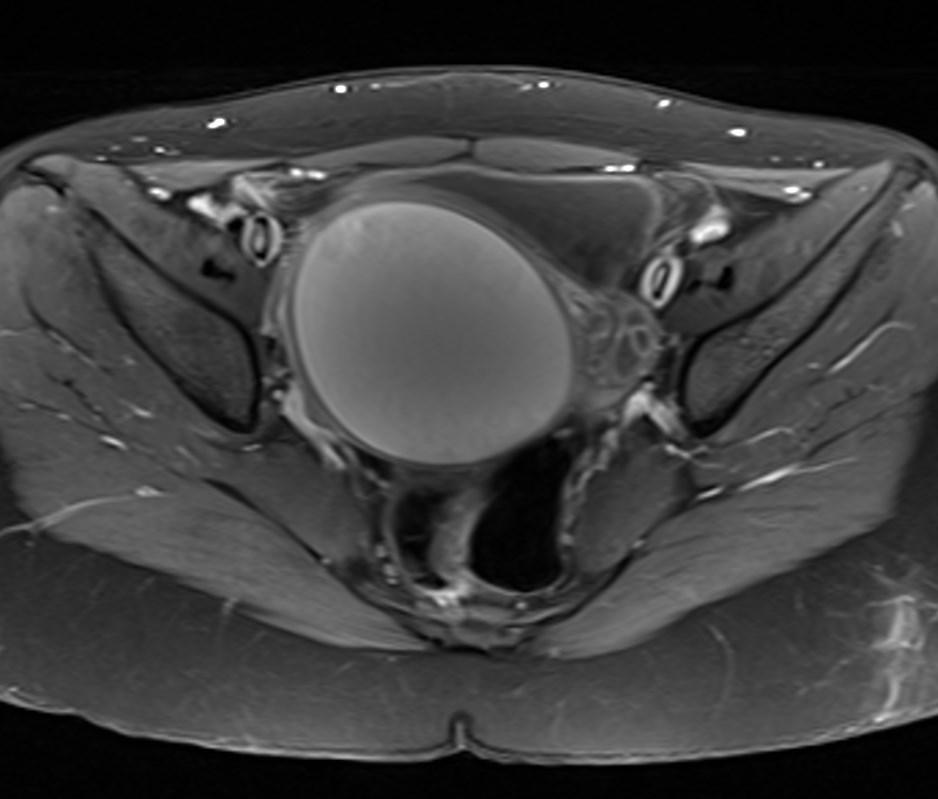

MR images showed hemorrhagic fluid in a distended vagina. The uterine cavity is not dilated.

In haematocolpos, there is accumulation of menstrual blood in the vagina in the setting of an anatomical obstruction, usually an imperforate hymen. When there is concurrent uterine distention, the term haematometrocolpos is used.